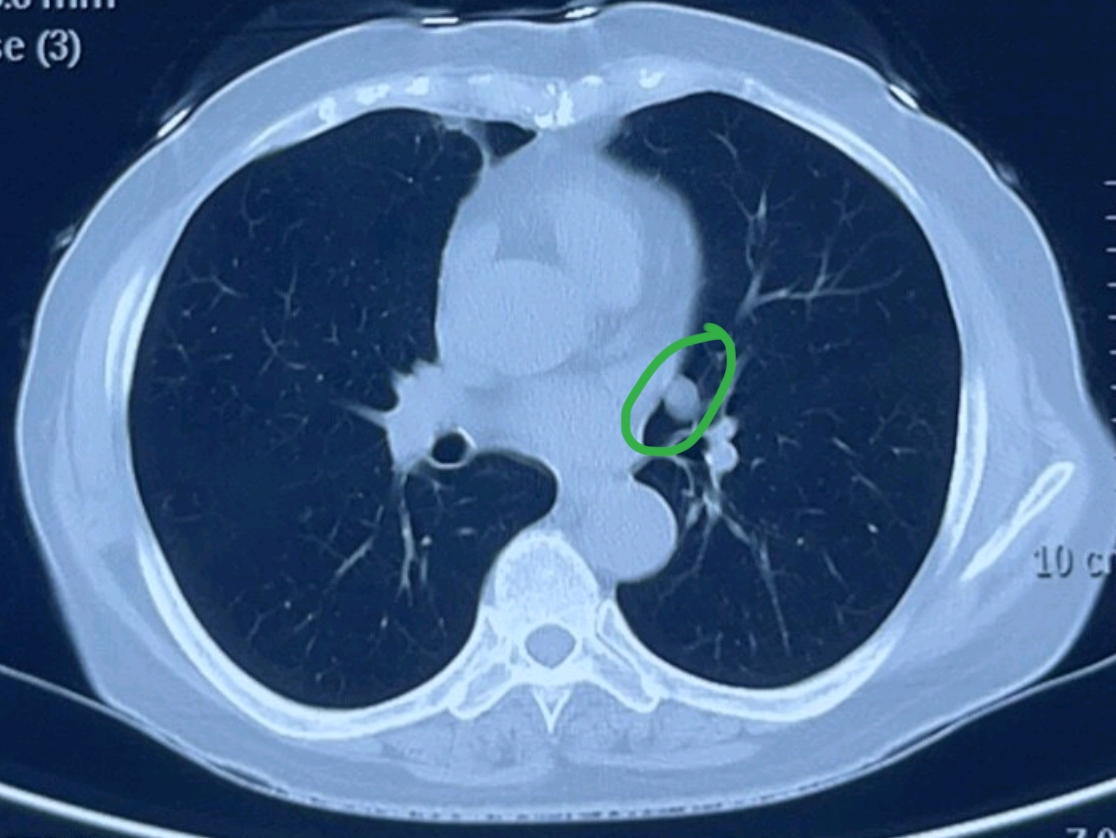

2、在民航招飞体检中,出现钙化灶是合格的自查及矫正方法自查招飞人员需要提前到当地医院做腹部超声和腹部CT扫描检查,以确定是否存在胆道系统结石或肝钙化灶等情况矫正如果检查出有任何问题,应按照医生叮嘱提早治疗,确保在招飞体检时符合相关标准要求例如,若发现有胆道系统结石,及时进行治疗,待无。